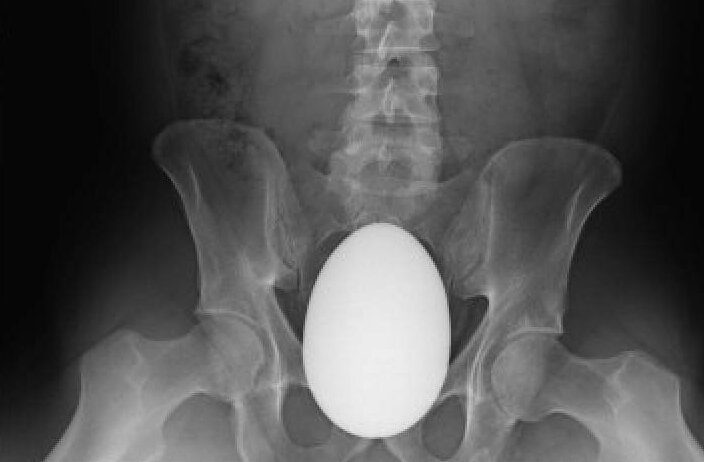

Может, была Пасха?

Яйцо наложили на снимок. Иначе должны быть видны внутренности яйца, какие-нибудь неоднородности. Сколько раз ходил на рентген, всегда заставляли снять или удалить ЛЮБЫЕ металлические предметы, поэтому с цепочкой и сережками НИКОГО не фотографировали.